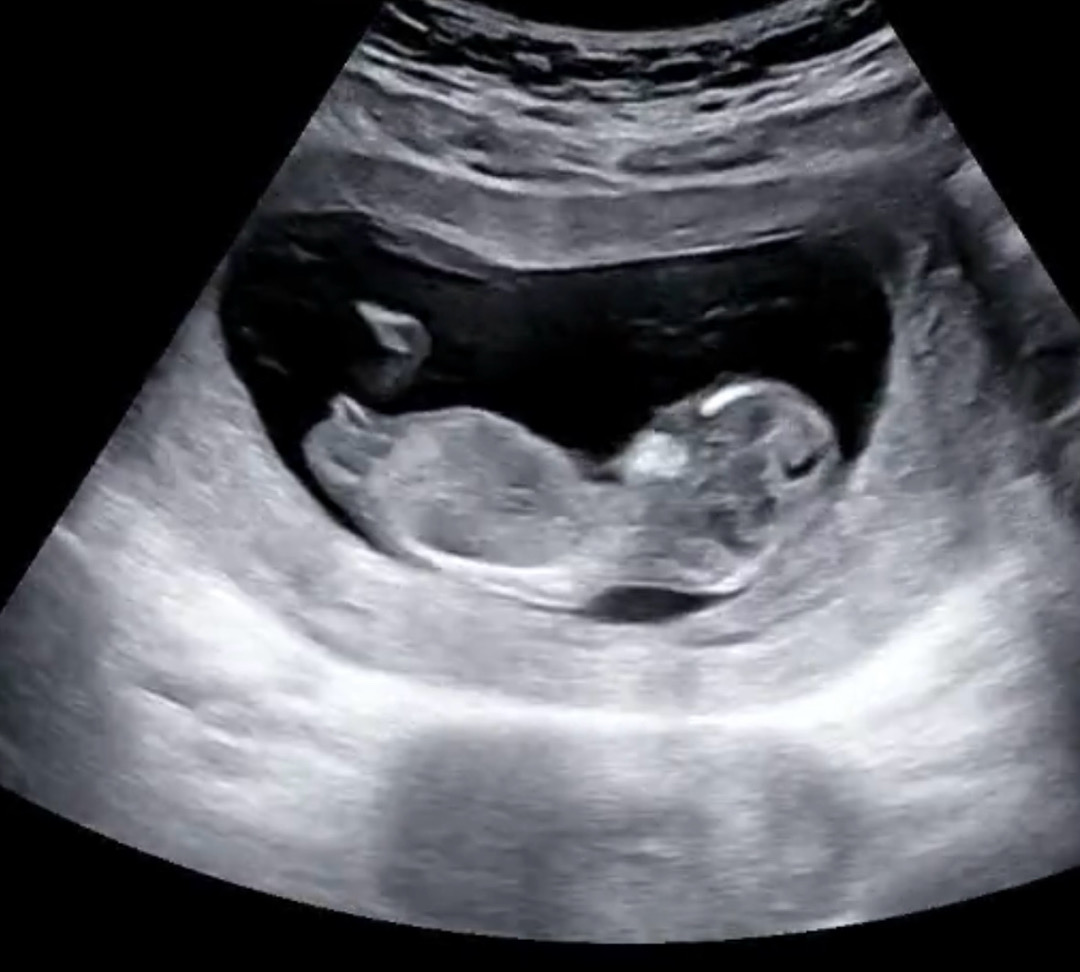

각도법봐주세요!!ㅠㅠ

12주3일차인데 알수 있을까요?

다들 봐주셔서 감사해여 ㅋㅋㅋ예상과 다르게 딸이었어요 ㅎㅎㅎㅎㅎ